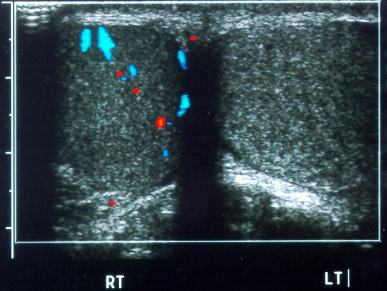

Kiểm tra siêu âm B được sử dụng rộng rãi trong chẩn đoán ung thư mũi họng và điều trị vì tính đơn giản, thuận tiện và vô hại. Bên cạnh việc kiểm tra di căn ung thư mũi họng đến các hạch bạch huyết ở cổ, nó cũng được sử dụng trong việc kiểm tra gan và hạch bạch huyết sau phúc mạc.